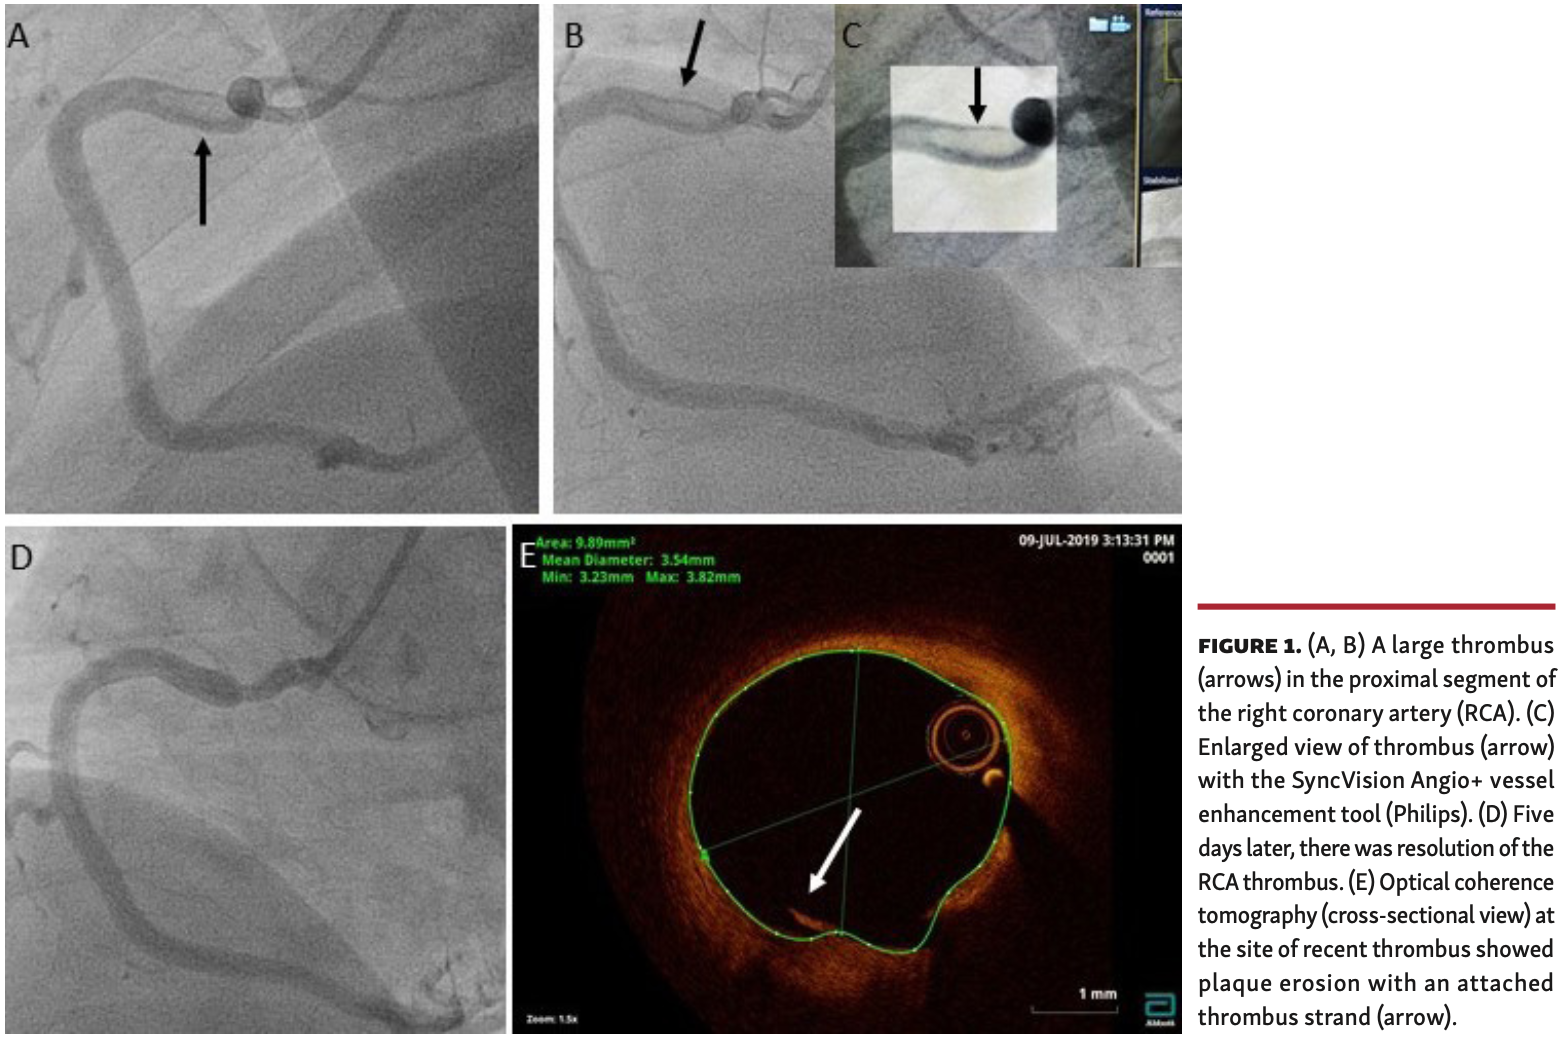

A 52-year-old man presented acutely with inferior ST-segment elevation myocardial infarction (STEMI). The left coronary system was unobstructed. The right coronary artery had Thrombolysis in Myocardial Infarction (TIMI) grade 3 flow throughout; however, angiography demonstrated a hazy oval filling defect proximally consistent with a large intracoronary thrombus (Figures 1A-1C). Given that the ST elevation was resolving and acknowledging the risk of distal coronary and/or systemic embolism, we deferred further intervention. The patient was transferred to the Coronary Care Unit on quadruple antithrombotic regime (aspirin, ticagrelor, tirofiban infusion for 48 hours, and enoxaparin). Transthoracic echocardiography demonstrated preserved systolic function.

Repeat coronary angiogram 5 days later showed resolution of the thrombus and TIMI 3 flow (Figure 1D). Optical coherence tomography (OCT) demonstrated at the site of recent thrombus a plaque erosion with an attached thrombus strand, but the lumen area was around 10 mm2 (Figure 1E). A conservative strategy was adopted and 1 year later the patient has remained well.